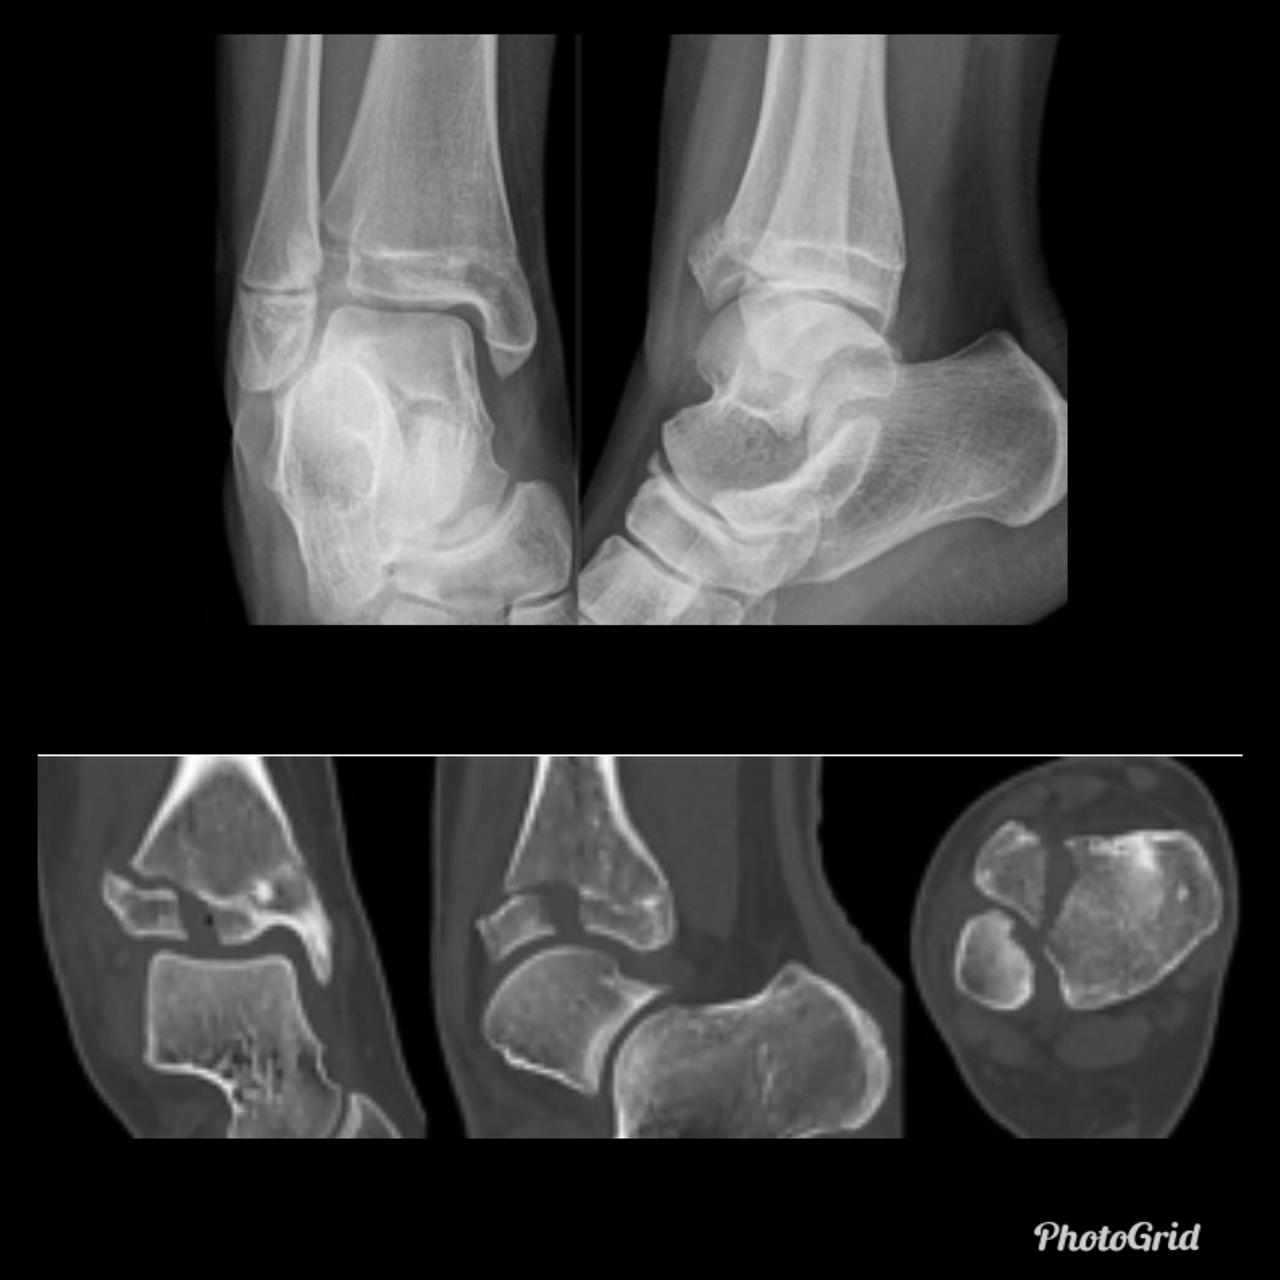

In the presented case there are destruction of talar head and neck with dislocation of talo-navicular joint, resorption of midfoot bones, subchondral sclerosis and multiple subchondral cysts on talocalcaneal aspect and cuboid facet of the calcaneum, progressive decrease of calcaneal inclination with typical rocker-bottom deformity, soft tissue swelling and arterial calcification. Bony debris are seen on dorsal aspect of the foot and posterior ankle joint. All findings are suggestive of Charcot neuro-osteoarthopathy, which is primarily an articular disease and most commonly located in the midfoot.

Unlike osteomyelitis, Charcot neuroarthropathy is primarily an articular disease and not related to overlying skin or soft tissue changes. Charcot neuroarthropathy commonly involves multiple midfoot bones. Features include joint instability, dislocation, destruction, disorganization, increased bone density, joint debris and deformity. Presence of subchondral cysts and intraarticular bodies with absence of the secondary signs for osteomyelitis support neuroarthropathy without infection.